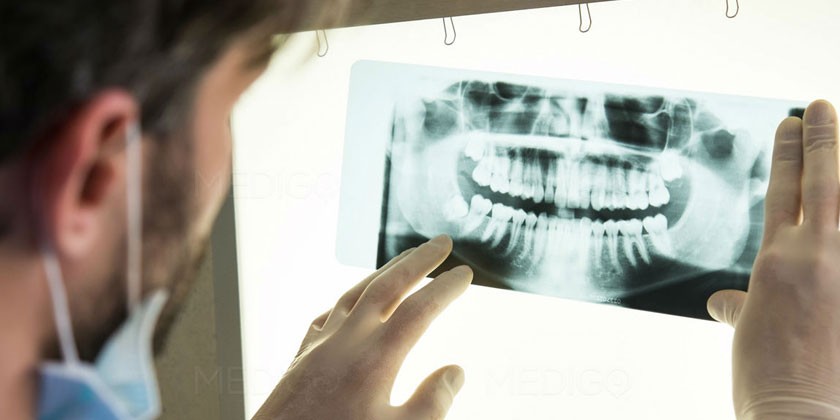

Диагностика гингивита

При наличии симптомов гингивита нужно обратиться к стоматологу или пародонтологу. Первым делом врач проводит опрос пациента, визуальный и инструментальный осмотр ротовой полости. Специалист обращает внимание на присутствие характерного налета и состояние десны вокруг зубов. Подтвердить гингивит помогают следующие функциональные тесты и методы диагностики:

- Пародонтограмма. Это исследование функционального состояния периодонта, десны, альвеолярных отростков – комплекса тканей, окружающих зуб и удерживающих его в альвеоле.

- Рентген. Необходим для проверки состояния костных тканей.

Для диагностики гингивита важно обратиться к стоматологу, который проведет осмотр полости рта и, при необходимости, назначит рентгенографию. Лечение гингивита включает медикаментозные препараты, такие как антисептические растворы и противовоспалительные препараты. Кроме того, врачи рекомендуют использовать народные средства, такие как прополис, календулу и эфирные масла, для укрепления здоровья десен.